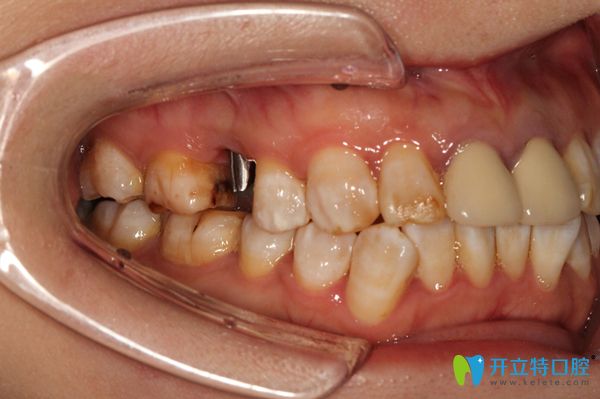

經(jīng)過了一系列的檢查后,開始種植牙手術,醫(yī)生技術真是嫻熟啊,錢女士感覺治療過程沒幾分鐘就好了,不過先放入種植體,張醫(yī)生就給錢女士放的是瑞士iti種植體。

放完種植體之后,醫(yī)生給錢女士戴的是臨時的牙冠,因為錢女士的口腔情況不適合即刻種植,所以,她需要三個月以后再來戴真正的牙冠。做完種植牙后,錢女士開心的說:“覺得自己年輕時候的那種咀嚼功能,又回來啦,真舒服”。